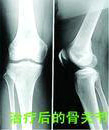

左脚治疗后X片